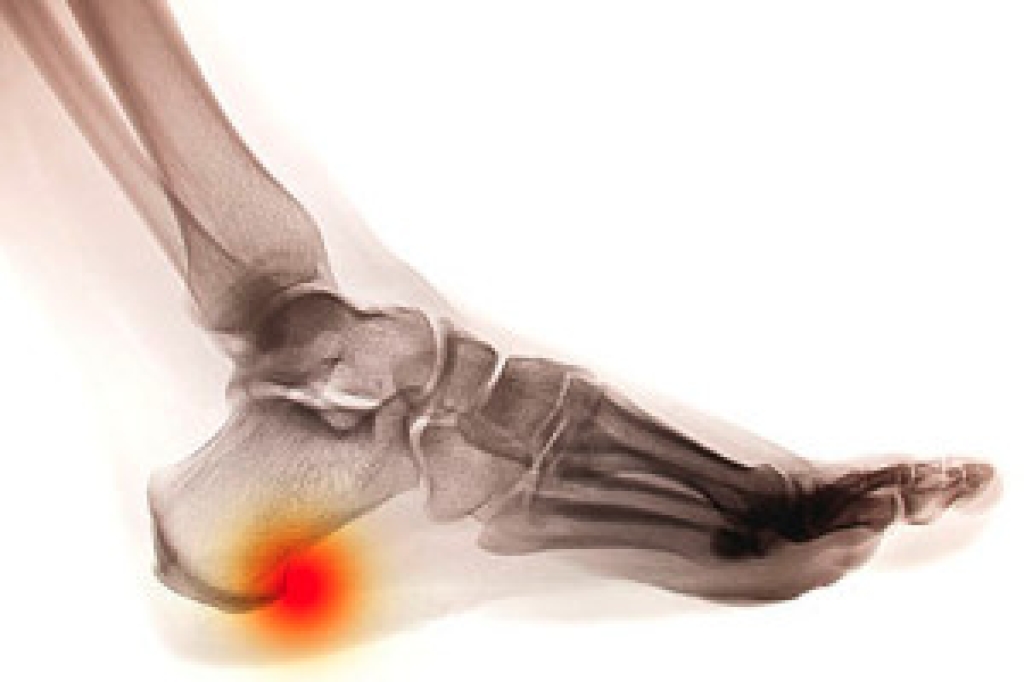

Although most people try to avoid foot trauma such as banging, stubbing, or dropping heavy objects on their feet, the unfortunate fact is that it is a common occurrence. Given the fact that toes are positioned in front of the feet, they typically sustain the brunt of such trauma. When trauma occurs to a toe, the result can be a painful break (fracture).

Symptoms of a Broken Toe

- Throbbing pain

- Swelling

- Bruising on the skin and toenail

- The inability to move the toe

- Toe appears crooked or disfigured

- Tingling or numbness in the toe

Generally, it is best to stay off of the injured toe with the affected foot elevated.

Severe toe fractures may be treated with a splint, cast, and in some cases, minor surgery. Due to its position and the pressure it endures with daily activity, future complications can occur if the big toe is not properly treated.